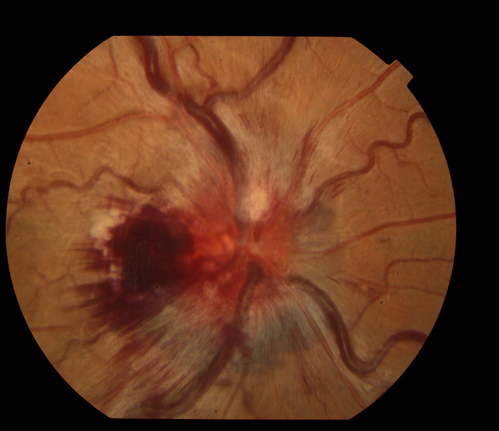

15 yrs old male presents with sudden onset of painless decreased vision in right eye x 6 days gradually worsening. No history of Trauma OD 20/30 OS 20/25, Diagnosis CRVO with ? Papilophlebitis

Central Retinal Vein Occlusion

Char Harris COA Midwest Eye Institute Indianapolis, IN

Topcon TRC50EX